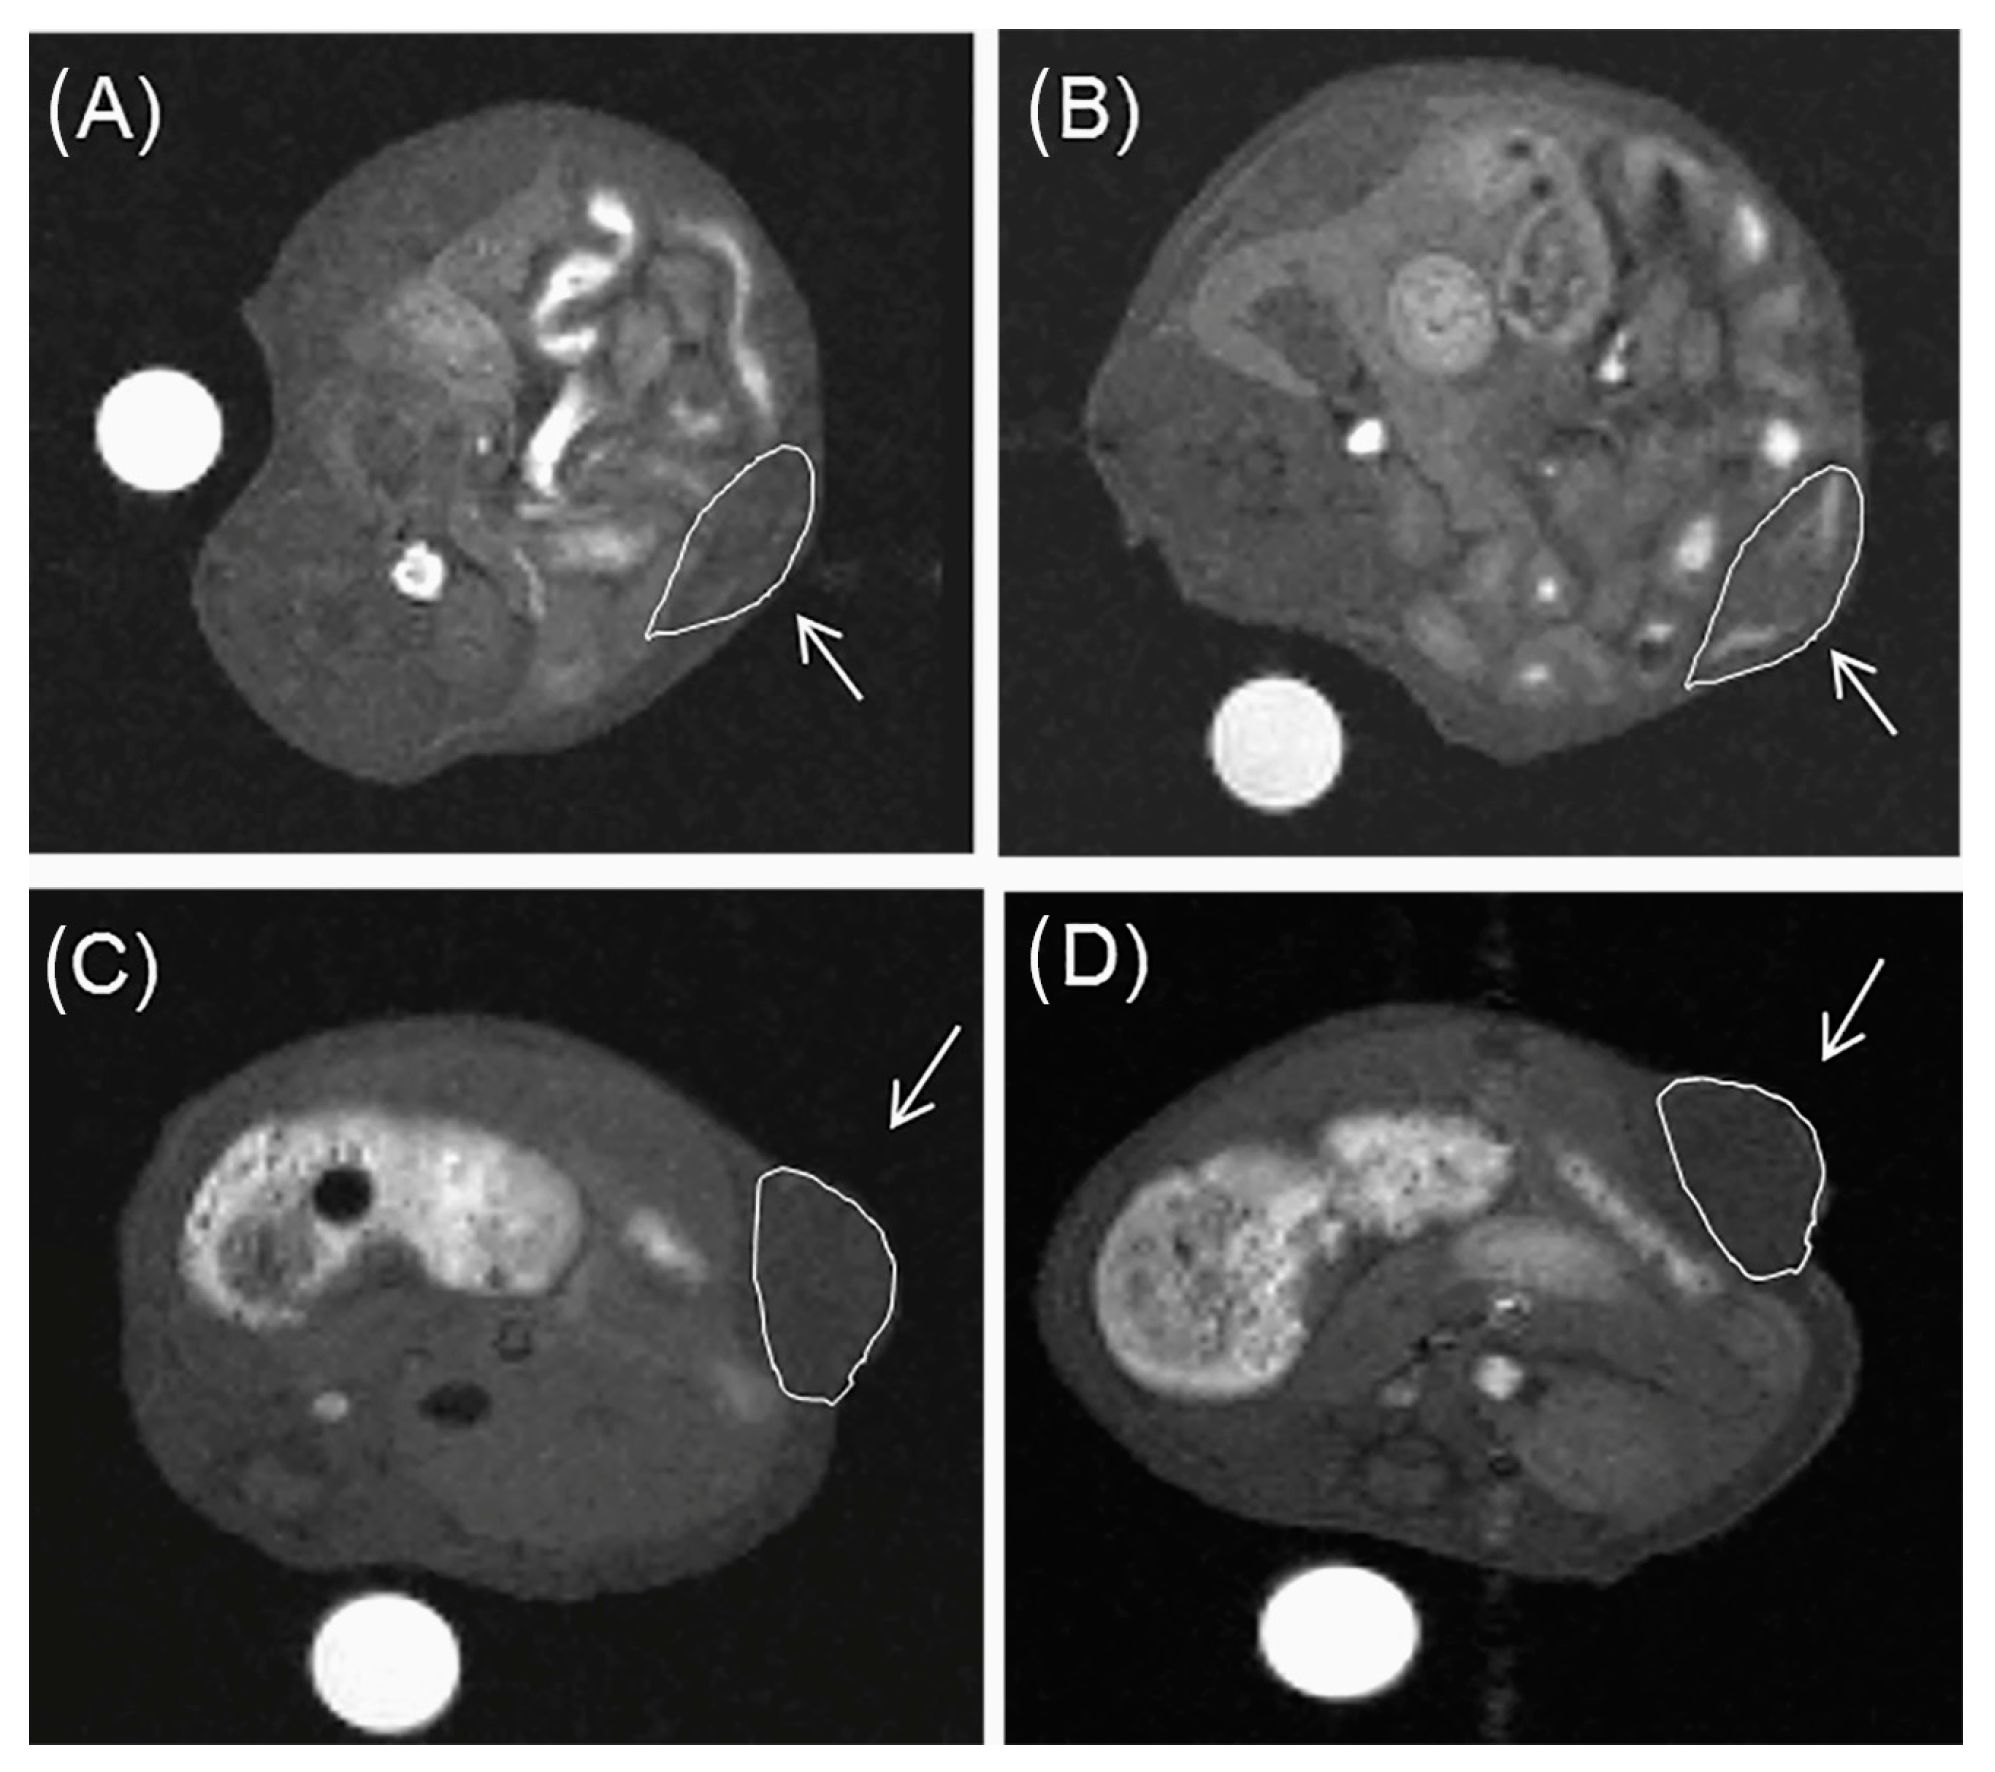

- Prata, M.I.M.; Santos, A.C.; Torres, S.; André, J.P.; Martins, J.A.; Neves, M.; García-Martín, M.L.; Rodrigues, T.B.; López-Larrubia, P.; Cerdán, S.; et al. Targeting of lanthanide (III) chelates of DOTA-type glycoconjugates to the hepatic asyaloglycoprotein receptor: Cell internalization and animal imaging studies. Contrast Media Mol. Imaging 2006, 1, 246–258. [Google Scholar] [CrossRef][Green Version]